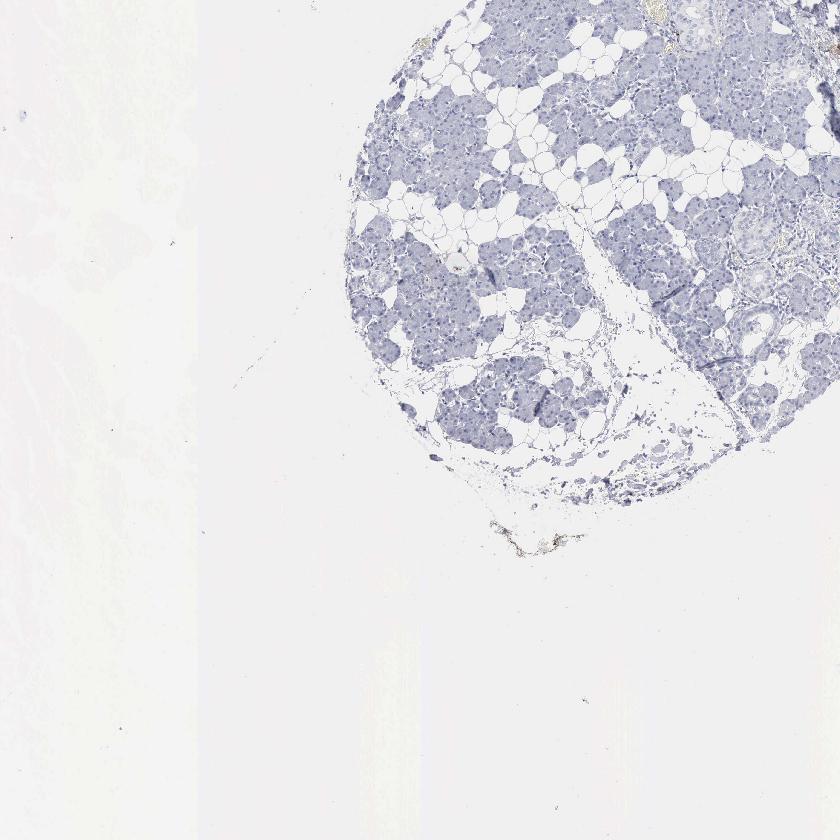

SALIVARY GLAND - Antibody stainingi

Antibody staining in the annotated cell types in the current human tissue is reported as not detected, low, medium, or high, based on conventional immunohistochemistry profiling in selected tissues. This score is based on the combination of the staining intensity and fraction of stained cells.

Each image is clickable and will lead to virtual microscopy that enables deeper exploration of all samples and also displays staining intensity scores, fraction scores and subcellular localization as well as patient and tissue information for each sample.

Antibody HPA052634Antibody CAB000363

Glandular cells Not detectedNot detected